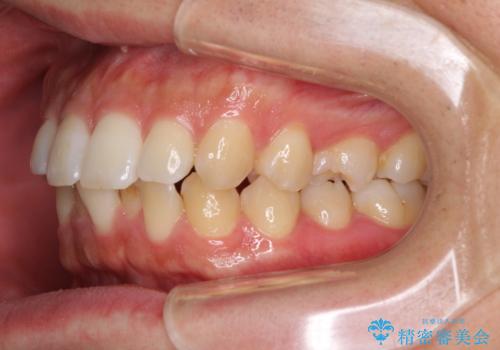

前歯のデコボコと突出感 インビザラインにて矯正治療

- 上下前歯のデコボコを気にして来院された患者様です。

インビザラインによる上下歯列の側方拡大と後方移動、IPR(歯と歯の間を削る)にるスペースの獲得により歯列を整えることとしました。

左上の小臼歯は捻転が強く、あえて180逆向きの状態で終了させる治療計画としました。

ご自宅と職場がともに遠方であったため、治療期間は長くなりましたが、患者様も我々も期待して以上に口元の突出感を改善することができました。